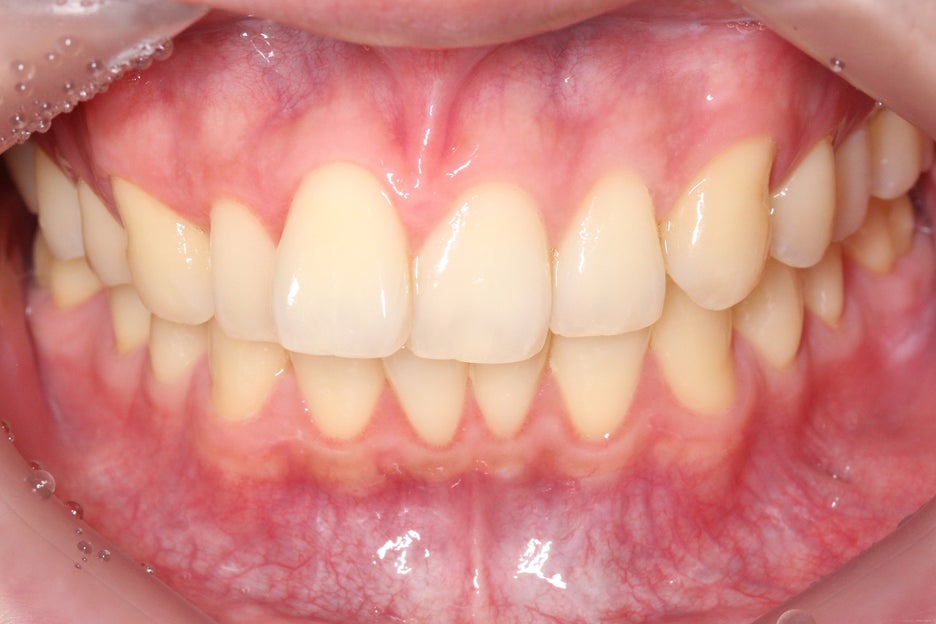

윗니 세라믹 교정 전

위의 Case를 보면 상악 부분교정 전

치아의 정중선이 크게 변위되어 있는 모습으로

상악이 좌측으로 돌아가 있는 듯한 모습인데요,

전치부를 약간 아랫쪽에서 바라본

overbite 사진에서도 정중선이

변위되어 있는 모습입니다.

또한 중절치가 가지런하게

배열되어 있지 않고 뻐드러지듯

돌출된 모습을 확인할 수 있는데요,

치아가 제대로 배열되기에 이 사이에

공간이 너무 좁아 비교적 늦은 시기에

맹출된 치아는 위와 같은 덧니처럼

뻐드러지는 증상이 나타날 수 있습니다.